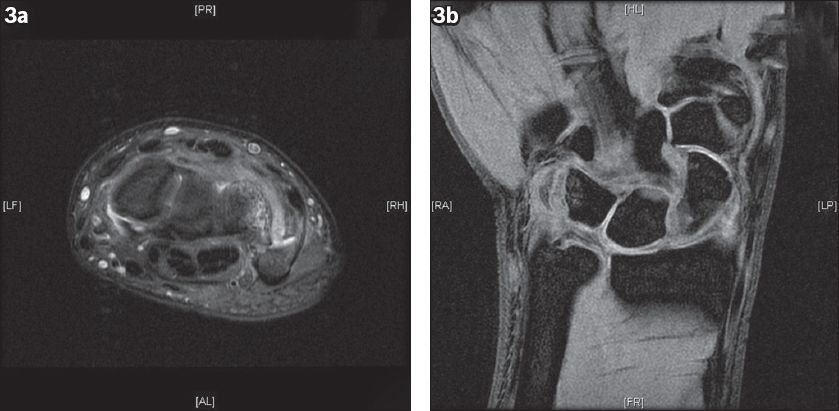

Fig. 3

(a–b) MR images of the right wrist show a fracture at the ulnar aspect of the pisotriquetral joint.